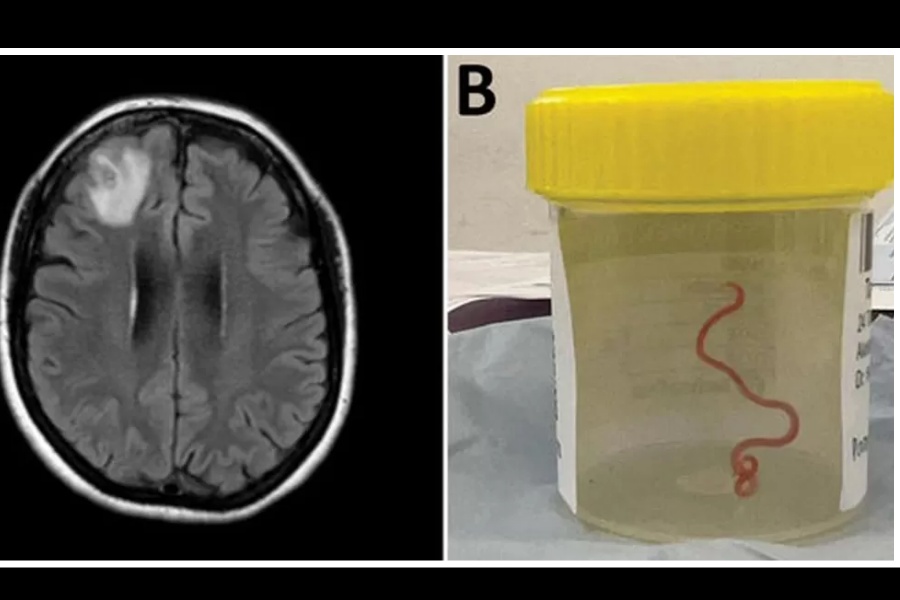

विश्वमै पहिलोपटक मानिसको मस्तिष्कमा जीवित कीरा भेटिएको छ। वैज्ञानिकहरूका अनुसार अष्ट्रेलियाकी एक महिलाको मस्तिष्कमा ८ सेन्टिमिटरको जीवितै किरा भेटिएको हो।

गत वर्ष क्यानबेरामा गरिएको शल्यक्रियामा ती महिलाकाे टाउकाको अगाडिको भाग (फ्रन्टल लोब)मा रहेको तन्तुबाट धागो (स्ट्रिङ) जस्तो किरा निकालिएको बीबीसीले जनाएको छ। ६४ वर्षीया ती महिलालाई पेट दुख्ने, खाेकी लाग्ने, बिर्सिने जस्ता समस्या एकसाथ देखिएपछि उनलाई अस्पताल भर्ना गरिएकाे थियाे। त्यहाँ उनकाे सीटी स्क्यान गरियाे। त्यसमा उनकाे मस्तिष्कमा जुका जस्तै देखिने कीरा खेलिरहेकाे देखिएपछि शल्यक्रिया गरिएकाे थियाे।

अनुसन्धानमा खटिएका डाक्टरका अनुसार अस्ट्रेलियामा पाइने एक प्रकारकाे अजिङ्गर (कार्पेट पाइथन)मा ओफिडास्कारिस रोबर्टसी नामकाे त्याे जुका सहजै भेटिन्छ। ती महिलाले आफू बसेको स्थान नजिकै तालको छेउमा एक प्रकारको स्थानीय घाँस, वारिगल ग्रीन्स सङ्कलन गर्दा त्याे जुका समातिएको हुनसक्ने उनीहरुकाे भनाइ छ।

इमर्जिङ इन्फेक्सियस डिजिज जर्नलमा लेख्दै अष्ट्रेलियका परजीवी विज्ञानका विज्ञ मेहराव हुसेनले ती महिलाले पाइथनको मल र परजीविका अण्डाहरूबाट दुषित घाँसका बिरुवाहरू प्रयोग गरेपछि उनलाई यस्तो संक्रमण भएको आशंका गरेका छन् ।

जनावरबाट मानिसमा सर्ने रोग र संक्रमणको बढ्दो खतरालाई यस तथ्यले उजागर गरेको अनुसन्धानकर्ताले चेतावनी दिएका छन्।